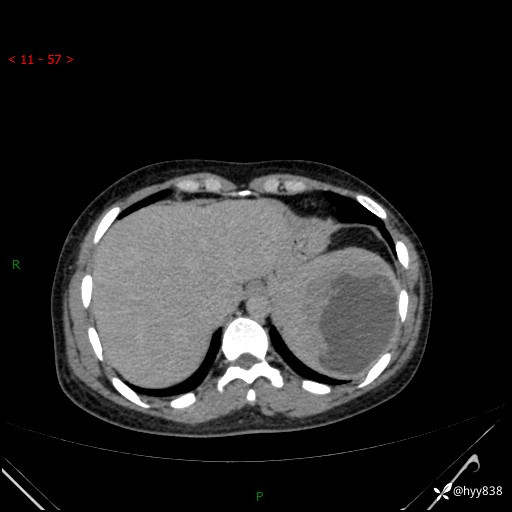

患者性别:男

患者年龄:44岁

主诉:外院超声发现脾脏占位,来我院进一步诊治。

辅助检查:CT

临床诊断:脾脏占位

脾脏CT平扫+增强(动脉期+静脉期)